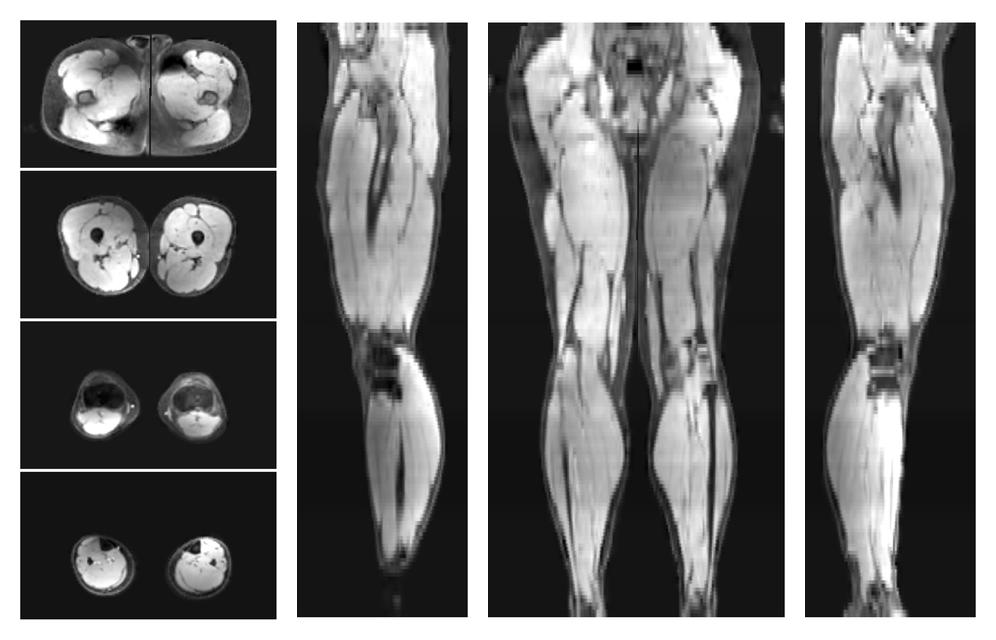

• Fat fraction

The fat fraction of the lower extremity obtained from the dixon reconstruction for muscle water fat quantification.

• R2 star relaxation

The R2 star relaxation time of the lower extremity obtained from the dixon reconstruction for muscle water fat quantification.